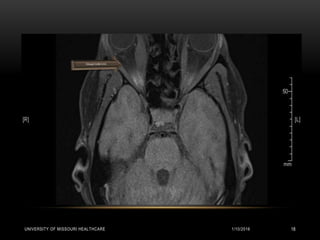

RADIOLOGY

CT Head:

• Scattered hyperdense foci visualized in bilateral basal ganglia and subcortical white

matter of the bilateral occipital lobes and within cerebellum. Right rectus muscle is slightly

more prominent. Findings consistent with Fahr’s disease.